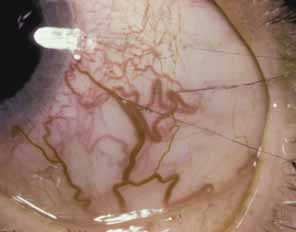

Vascular anomalies of the iris can present as persistence of the tunica vasculosa lentis or as irregularly wandering superficial anomalous iris vessels. The first condition exhibits a regular arrangement of vessels looping into the pupillary axis in front of or behind the lens. Normal radial vessels on the iris surface are also prominent be-cause there is usually hypoplasia of the anterior iris stroma.

In the second condition, anomalous superficial iris vessels wander irregularly over the iris surface with an often distorted pupil (Fig. 4). The iris surface has a whorled appearance and the anterior iris stroma is often hypoplastic. These vascular anomalies differ from the normal exposure of radial iris vessels seen in lightly pigmented eyes. Anomalous iris vessels are seen most frequently in eyes that present with glaucoma and cloudy corneas at birth, and are not associated with any particular syndrome. It is unclear whether they represent an earlier onset of primary congenital glaucoma or an entirely different syndrome. They do indicate a more severe malformation of the anterior segment and a grave prognosis, with such cases requiring multiple surgeries.

Fig. 4 Anomalous iris vessels. Vessels course irregularly over the iris surface. On the right, small vessels are seen crossing the pupillary margin. The pupil is distorted at the 10 o'clock position. Radial iris fibers are curved and irregularly arranged.